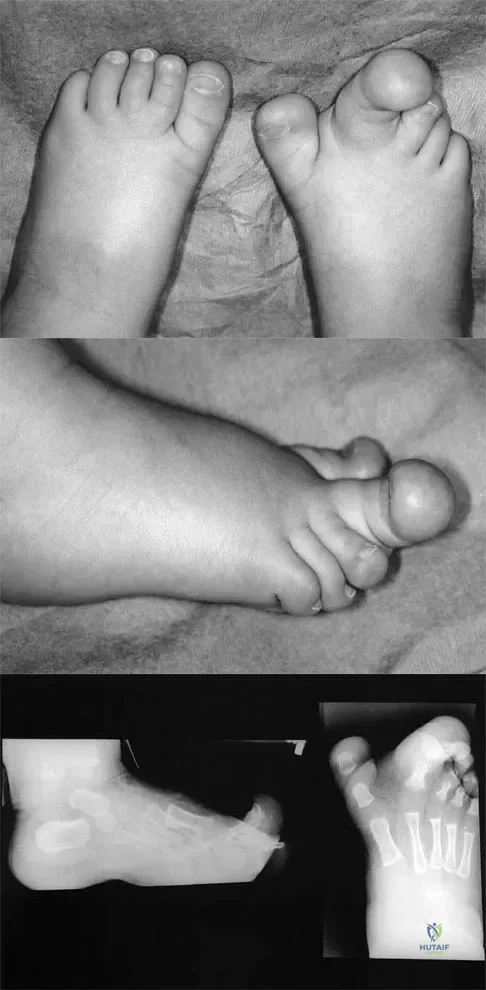

Figures 4a through 4c show the clinical photographs and radiographs of a 12-month-old boy who has progressive difficulty wearing shoes because of the length of the second toe, as well as width of the forefoot. Management should consist of

Explanation